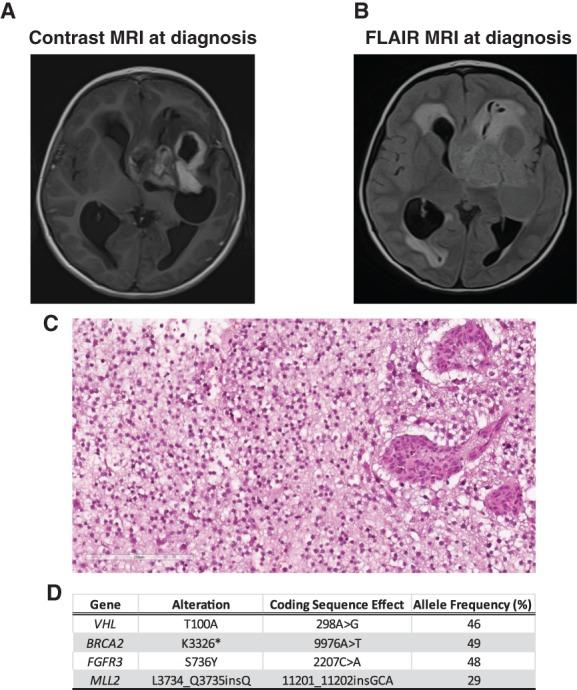

For pediatric patients with high-grade gliomas, standard-of-care treatment includes surgery, chemotherapy, and radiation therapy; however, most patients ultimately succumb to their disease. With advances in genomic characterization of pediatric high-grade gliomas, the use of targeted therapies in combination with current treatment modalities offer the potential to improve survival in this patient population. In this report, we present the case of a 3-year-old girl with glioblastoma who continues to experience an exceptional and durable response (>2 years) to the poly (ADP-ribose) polymerase (PARP) inhibitor olaparib. Our patient presented with persistent and progressive seizure activity that upon workup was the result of a large heterogeneously enhancing, mixed cystic and solid mass in the left frontal-parietal-temporal region. Histopathologic analysis of resected tumor tissue confirmed the diagnosis of glioblastoma, and comprehensive genomic profiling demonstrated absence of any BRAF or H3F3A mutations. Genomic profiling, however, did reveal a probable germline heterozygous BRCA2 Lys3326Ter (K3226*) nonsense variant. After debulking surgery, the patient received standard-of-care treatment with radiation and temozolomide. Nine months later the PARP inhibitor olaparib was administered in combination with temozolomide for 16 cycles. This regimen was well tolerated by the patient and serial imaging showed reduction in tumor size. Since completion of the regimen, the patient remains neurologically intact with no evidence of tumor recurrence. To our knowledge, this represents the first case of a pediatric glioblastoma that maintains a durable response to a therapeutic strategy that included the PARP inhibitor olaparib and more generally highlights the potential clinical utility of incorporating these agents into the treatment of pediatric high-grade gliomas. KEY POINTS: Germline mutations detected in pediatric gliomas may represent a cancer predisposition syndrome. Integrating molecular testing into routine clinical care for pediatric patients with glioma is critical to identify therapeutic targets and patients with a cancer predisposition syndrome. Patients with glioma with defects in DNA repair pathway components (e.g., BRCA1/2) may show increased responsiveness to poly (ADP-ribose) polymerase (PARP) inhibitors. Combining PARP inhibitors with temozolomide (standard-of-care treatment) revealed no adverse events or toxicities over the course of 18 months.

对于患有高级别神经胶质瘤的儿科患者,标准治疗包括手术、化疗和放射治疗;然而,大多数患者最终仍会死于该疾病。随着儿科高级别神经胶质瘤的基因组特征的进步,靶向治疗与当前治疗方式的结合为改善该患者群体的生存率提供了可能。在本报告中,我们介绍了一例 3 岁女孩的病例,她在接受聚(ADP-核糖)聚合酶(PARP)抑制剂奥拉帕利治疗后,继续表现出异常和持久的反应(>2 年)。该患者表现为持续性和进行性癫痫发作,经检查发现左额顶颞叶区有一个大的异质性增强、混合囊性和实性肿块。切除肿瘤组织的组织病理学分析证实了胶质母细胞瘤的诊断,全面的基因组分析显示没有任何 BRAF 或 H3F3A 突变。然而,基因组分析确实显示了一种可能的种系杂合 BRCA2 赖氨酸 3326 终止(K3326*)无意义变异。在肿瘤减灭手术后,患者接受了标准的放射治疗和替莫唑胺治疗。9 个月后,奥拉帕利联合替莫唑胺治疗 16 个周期。该方案患者耐受良好,连续影像学检查显示肿瘤体积缩小。自该方案完成以来,患者神经功能完整,无肿瘤复发迹象。据我们所知,这是首例儿科胶质母细胞瘤患者对包括 PARP 抑制剂奥拉帕利在内的治疗策略保持持久反应的病例,更广泛地强调了将这些药物纳入儿科高级别神经胶质瘤治疗的潜在临床应用。要点:在儿科胶质瘤中检测到的种系突变可能代表一种癌症易感性综合征。将分子检测纳入儿科胶质瘤患者的常规临床护理中对于确定治疗靶点和癌症易感性综合征患者至关重要。具有 DNA 修复途径成分缺陷(例如,BRCA1/2)的胶质瘤患者可能对聚(ADP-核糖)聚合酶(PARP)抑制剂显示出更高的反应性。在 18 个月的时间里,PARP 抑制剂联合替莫唑胺(标准治疗)没有发现不良反应或毒性。